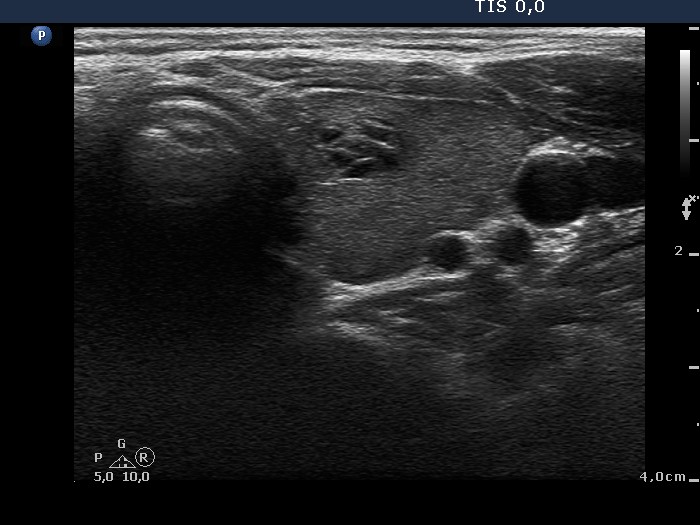

Benign Hashimoto's thyroiditis (cytological diagnosis) - case 1652

First, we demonstrate two cases of Hashimoto's thyroiditis with pronounced fibrotic changes. Both present pale and bright hyperechogenic granules and lines corresponding to normal and excessive connective tissue. Neither of the discrete areas are nodules in a pathological sense.